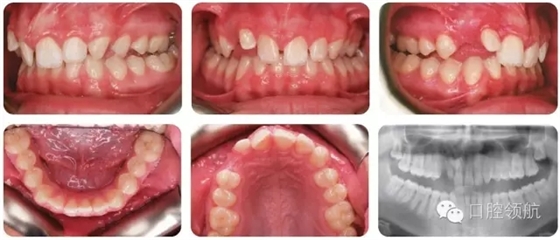

該患者錯牙合特點(diǎn)(圖2.38)是什么?

● II類2分類切牙關(guān)系。

● 覆牙合較深。

● 中線不調(diào)(上中線右偏2mm)。

● 后牙近中尖對尖關(guān)系(雙側(cè))。

● 上牙弓中度擁擠。

● UR3未萌,可能與UR2異位。